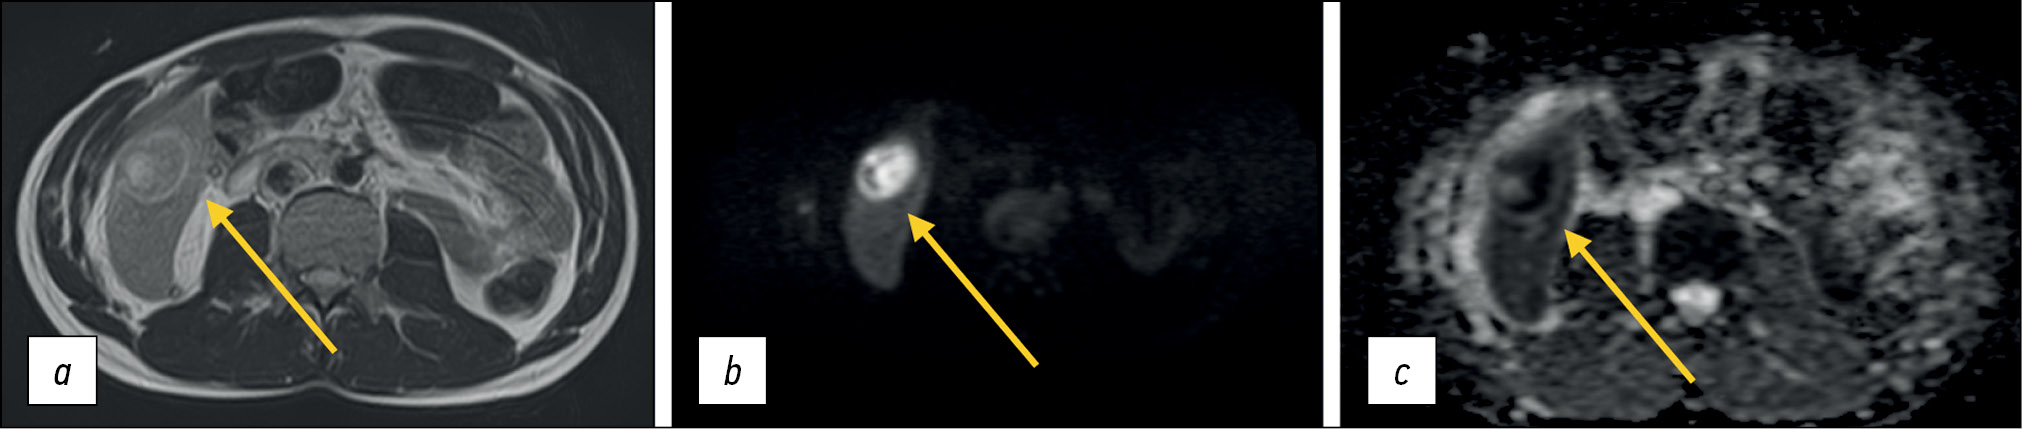

Diffusion is proportional to cell density and cell membrane integrity: restricted diffusion is observed in tissues with increased cellularity or decreased extracellular fluid volume (e.g., some tumors and abscesses; Fig. 4) and in the presence of cytotoxic edema. Relatively free diffusion is observed in tissues with low cell density or when their membranes are damaged, such as cysts or necrotic tissues.

Figure 4. Abdominal magnetic resonance imaging, encapsulated liver mass (abscess) (arrows): а Т2-weighted image; b apparent diffusion coefficient; с map of apparent diffusion coefficient.